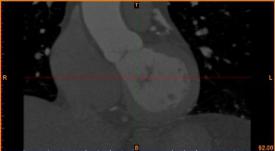

病人的冠脈造影CT數(shù)據(jù) 提取出的冠脈三維數(shù)據(jù)